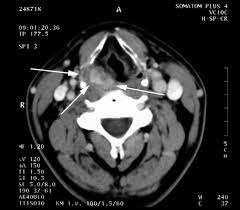

Figures from www.medscape.org She is diagnosed with stage iv lung cancer with rib cage bone metastasis. One primary neck cancer that might be seen on a neck scan is thyroid cancer. If your doctor suspects that you have cancer near your abdomen, they may recommend an abdomen ct scan. My mom (age:64) asian diagnosed with lung cancer.summary: Its purpose is to provide digital images of the inside of the colon and document the size and location of abnormalities. Computed tomography (ct) scans detect tumors, but do not determine whether they are malignant or not. Don't eat or drink anything for 3 to 4 hours before your scan. Computed tomography scan, ct scan, cat scan, and spiral or helical ct.

One primary neck cancer that might be seen on a neck scan is thyroid cancer.

Ct Scans Are The Best Alternative To Colonoscopy To Investigate Bowel Cancer Imperial News Imperial College London from www.imperial.ac.uk Biopsy is one of the way to figure out the cause of findings on ct scan. A quick and painless lung ct scan can play a crucial role in catching lung cancer and other abnormalities earlier for better treatment options. The abdomen and pelvis contain the digestive organs as well as the urinary, endocrine, and reproductive systems. Before your scan you may need to drink either half a litre of water or a type of dye called a contrast medium. The scan is painless and takes about 10 to 30 minutes. This depends on the reason for your ct scan and which part of your body your doctor needs to see. The neck is an anatomically complicated region with many internal structures. Hello, thank you for using healthcaremagic to post your health query.